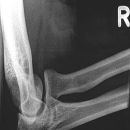

Ellenbogen seitlich (2. Ebene radio-ulnar)

Beurteilungskriterien

- Weichteilzeichen: Verlagerung des ventralen (proximal der Fossa coronoidea bis 5mm breit ist normal) und dorsalen distalen Humerusfettkörpers (normalerweise nicht sichtbar), Supinatorfettlinie: normalerweise etwa 3-4cm lang und 2-3mm breit, parallel zum proximalen Radius

- Target areas: vordere und hintere Humeruskontur, Radiusköpfchen, Processus coronoideus (evtl. zusätzlich 45°-Schrägaufnahme), Olecranon, harmonische Darstellung des Radiusköpfchen? Impressionen? Stufe? Verdichtungen, Fissur? Knickbildung?

- Auftreten, Verschmelzung und Lokalisation der Epiphysenkerne -> Verlagerung? vgl. Anatomie Kids! Viele kindliche Verletzungen sind anhand der Verlagerung der Knochenkerne differenzierbar! Evtl. Vergleich mit Gegenseite oder MRT hilfreich.

- Täuschungsmöglichkeiten: Persistierende Apophysen an Olecranonspitze oder Processus coronoideus, Kortikaliseinkerbungen als Residuen der Epiphysenfugen (v.a. des Olecranons)

- Kids: Kreuzung vordere Humeruslinie mit Radiushalsachse im mittleren Capitulumdrittel? Abweichung -> dislozierte, supracondyläre Humerusfraktur? Epiphysenfugenverletzung? Dislokation des proximalen Radius? Luxation?

Cave:

- 50% der Radiusköpfchenfraktur sind nicht disloziert und u.U. nicht nachweisbar -> bei klinischem Verdacht ist ein positives Fettpolsterzeichen nahezu beweisend! Greenspan-Aufnahme, evtl. CT oder MRT!

- Distale Humerusfraktur (Trochlea oder Capitulum) mit frontaler Bruchebene -> "Halbmondzeichen" durch plankonvexe(s) und in die Fossa cubiti dislozierte(s) Fragment(e) -> CT zur Beurteilung der Gelenkflächenverhältnisse.

- Komplexe Frakturen, Gelenkflächenverhältnisse? -> CT